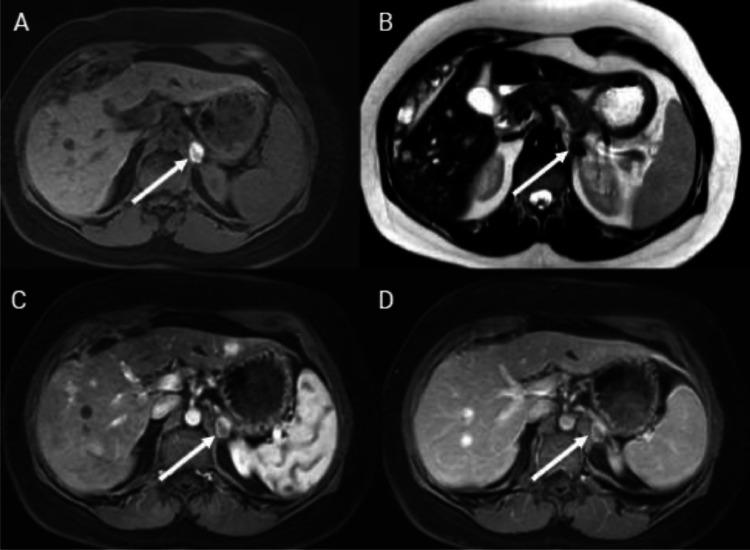

This case report describes the radiofrequency (RF) ablation of a pheochromocytoma in a 35-year-old female with multiple endocrine neoplasia (MEN) II syndrome, who previously underwent a right adrenalectomy and thyroidectomy. The patient presented with a new tumor in the left adrenal gland, detected via imaging, without evidence of metastasis. Opting against surgical adrenalectomy due to previous surgeries, she underwent RF ablation after preparatory alpha and beta blockader. During RF ablation, a hypertensive crisis occurred, managed effectively with nitroprusside sodium and supportive measures. Postprocedure recovery was uneventful, with normal metanephrine levels and imaging indicating successful ablation. This report highlights the feasibility and challenges of using RF ablation for adrenal pheochromocytoma, suggesting a potential shift towards less invasive management for select cases.

本病例报告描述了一名患有多发性内分泌腺瘤病(MEN)II 综合征的 35 岁女性嗜铬细胞瘤的射频(RF)消融治疗情况。该患者此前接受过右肾上腺切除术和甲状腺切除术。通过影像学检查发现患者左肾上腺有一个新肿瘤,且无转移迹象。由于既往手术史,患者未选择手术切除肾上腺,而是在进行了α和β受体阻滞剂预处理后接受了射频消融治疗。在射频消融过程中发生了高血压危象,通过硝普钠和支持措施得到了有效控制。术后恢复顺利,甲氧基肾上腺素水平正常,影像学检查显示消融成功。本报告强调了使用射频消融治疗肾上腺嗜铬细胞瘤的可行性和挑战,提示对于某些病例可能会转向侵入性较小的治疗方式。